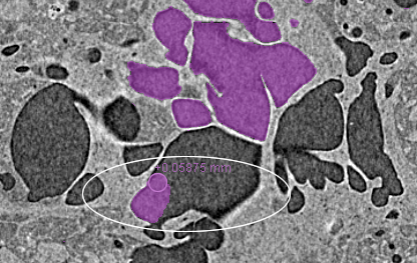

- Select a class in the Classes and scalar information box and then label the voxels corresponding to that class.

For example, you may need to label voxels that correspond to a specific material type or phase or to an anatomical structure.

- Label voxels that correspond to the other classes included in the multi-ROI, as required.

Note The number of labeled voxels that correspond to each class is indicated in the Labeled Voxels column and is updated dynamically while you work.

Labeled voxels cannot intersect. For example, if you are labeling voxels as 'Class 1' and paint over labeled voxels of another class, then those voxels will be automatically labeled as 'Class 1'.